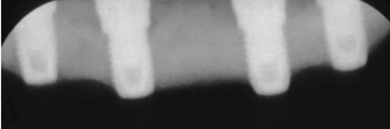

Fig 2. Four vertical machined-surface osseointegrated implants placed in 1983 penetrated the inferior cortex up to 3 mm to 4 mm in depth, immediate postoperative.

Figure 2

Fig 3. At 4 years and 5 months follow-up, reparative bone had formed to the apices of all implants.

Figure 3

The Toronto Conference in 1982, chaired by Professor George Zarb and presented by Professor Per-Ingvar Brånemark, was a seminal event that changed edentulous treatment planning concepts irrevocably. No longer was it necessary to rebuild lost bone through grafting alone in either arch. The severely atrophic mandible, for example, could be treated with as few as four implants used to support a bone-sparing prosthesis through integrated tooth analogs, as demonstrated in Figure 1 through Figure 3. Here, an 81-year-old patient presented with severe mandibular atrophy (Figure 1) from denture wear since a very young age and had a history of being unable to manage a mandibular prosthesis despite numerous attempts at new denture construction. Four vertical machined-surface osseointegrated implants were placed in 1983 by Professor Brånemark, and all four penetrated the inferior cortex up to 3 mm to 4 mm in depth, as shown on the immediate postoperative panoramic film (Figure 2). At 4 years and 5 months, reparative bone had formed to the apices of all implants (Figure 3), and all of them remained in uncompromised function until the patient passed away at age 90.